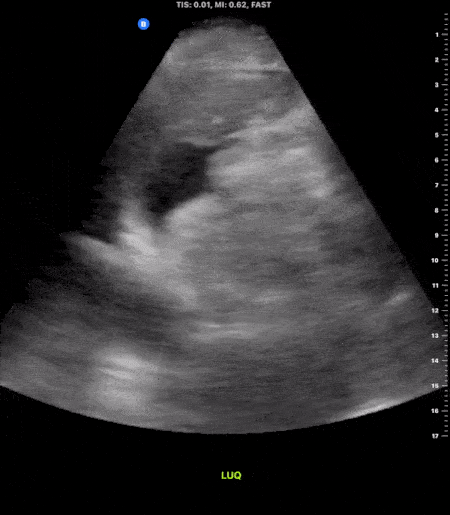

Trauma - Positive LUQ View

This image demonstrates free fluid present in the left upper quadrant following blunt trauma to the abdomen. Notice the anechoic area present along the the pericolic gutter as well as between the spleen and the diaphragm consistent with free fluid. Michael Macias, MD